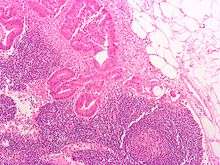

Micrograph of a colorectal adenocarcinoma metastasis to a lymph node. The cancerous cells are at the top center-left of the image, in glands (circular/ovoid structures) and eosinophilic (bright pink). H&E stain.